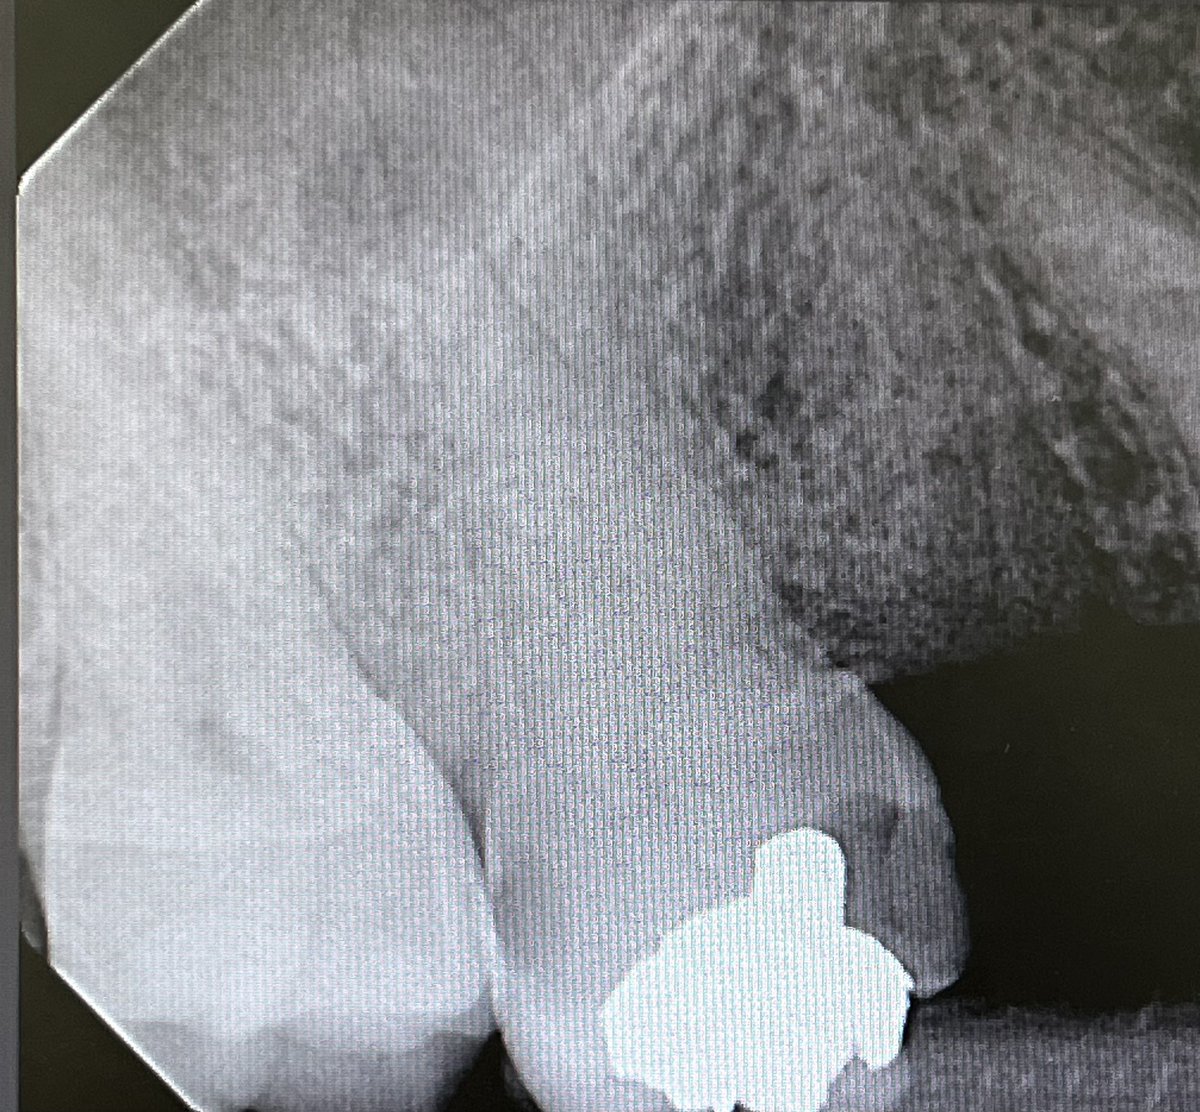

Dx:

24: Symptomatic irreversible Pulpitis w/ SAP

TX:

Non-Surgical RCT (One Visit)